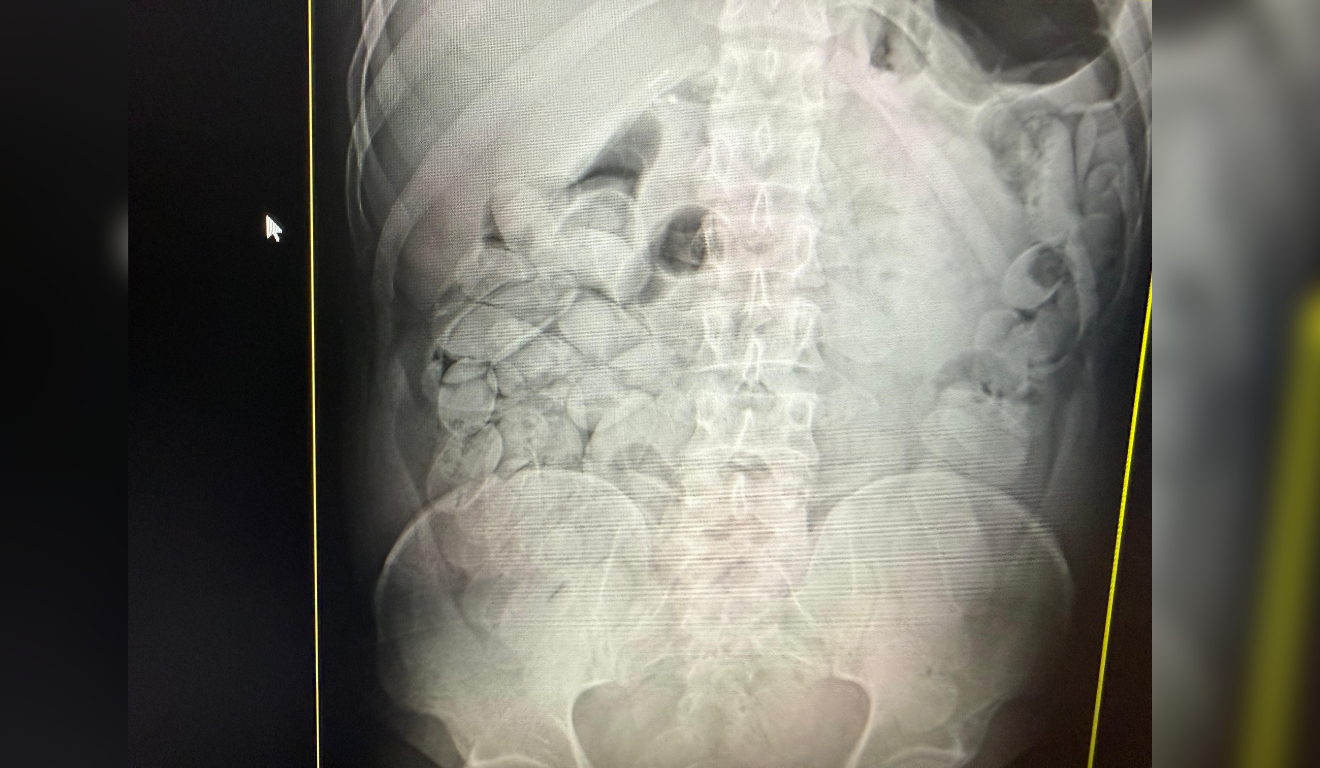

De acordo com os órgãos de fiscalização, exames médicos confirmaram que 17 passageiros haviam ingerido cápsulas de substância semelhante à pasta base de cocaína. Ao todo, cerca de 20 quilos da droga foram apreendidos. A mercadoria é avaliada em aproximadamente R$ 1 milhão.

Os detidos permaneceram sob custódia médica no pronto-socorro municipal até a eliminação total das cápsulas ingeridas. Após os procedimentos médicos, eles seriam encaminhados à polícia judiciária. Um dos suspeitos já foi apresentado à Polícia Federal.